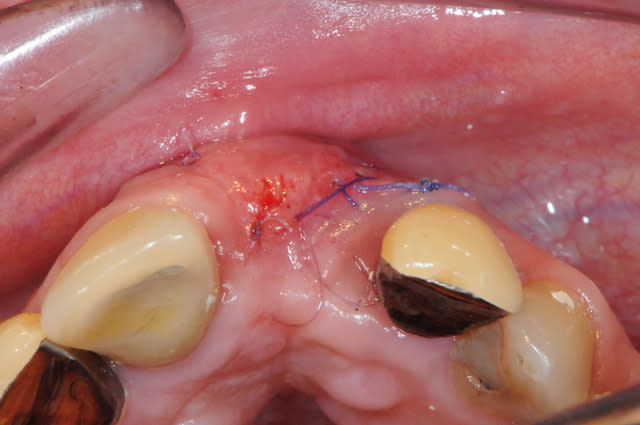

Voila un exemple de conjonctif pédiculé palatin.

Les gros avantages par rapport à ta technique sinclair sont :

1- mobilisation d'un plus gros volume de tissus pour gonfler en vestibulaire.

2- cicatrisation de première intention au niveau du palais puisque l'ensemble du site prélevé est couvert par ta fenêtre d'accès

3- peu de suite post opératoire.